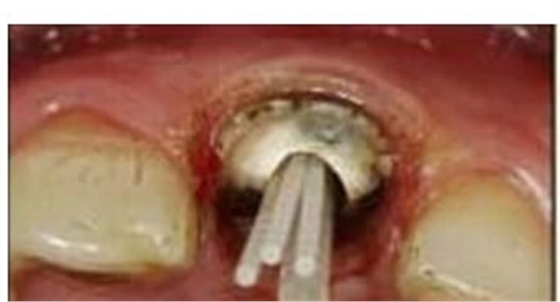

大多數(shù)醫(yī)生在樁道預(yù)備時(shí)習(xí)慣于干燥預(yù)備根管(圖 1),這樣很容易破壞根管壁的牙本質(zhì)結(jié)構(gòu),同時(shí)也可形成較厚的玷污層,影響樹脂水門汀與牙體組織的粘接。因此,臨床操作時(shí)應(yīng)選擇沖洗的方法冷卻預(yù)備根管(圖 2),防止牙膠及封閉劑粘連附著于根管壁形成第二玷污層(根管治療時(shí)形成的玷污層稱為第一玷污層),有利于樹脂水門汀與根管牙本質(zhì)的粘接。

圖1:干燥預(yù)備根管。 圖2:沖洗預(yù)備根管。